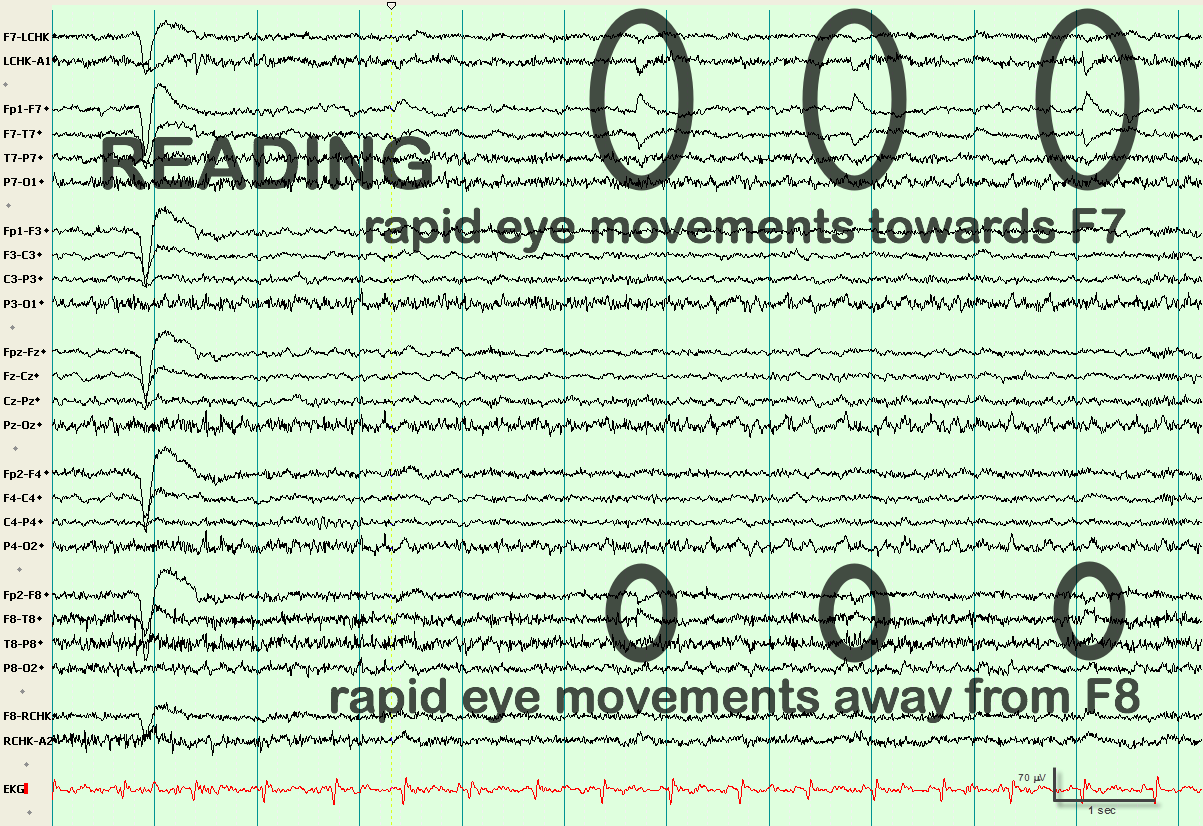

Roving Eye Movements

eegatlas-online.com

eegatlas-online.com

artifacts eye roving movements eegatlas online

| Lateral Eye Movements And Eye Blinks Recorded Simultaneously With

www.researchgate.net

www.researchgate.net

movements blinks recorded simultaneously eog bipolar

Lateral Eye Movement Although A Horizontal, Frontal Dipole Is The Key

www.pinterest.com

www.pinterest.com

eye movement eeg lateral horizontal key bullet journal

Lateral Eye Movement

eegatlas-online.com

eegatlas-online.com

artifacts eye movement lateral eegatlas online

Lateral Eye Movement

eegatlas-online.com

eegatlas-online.com

eye lateral movement artifacts eegatlas online

Lateral Eye Movement

eegatlas-online.com

eegatlas-online.com

artifacts eye movement lateral eegatlas online

Lateral Eye Movement

eegatlas-online.com

eegatlas-online.com

eye movement lateral artifacts online eegatlas